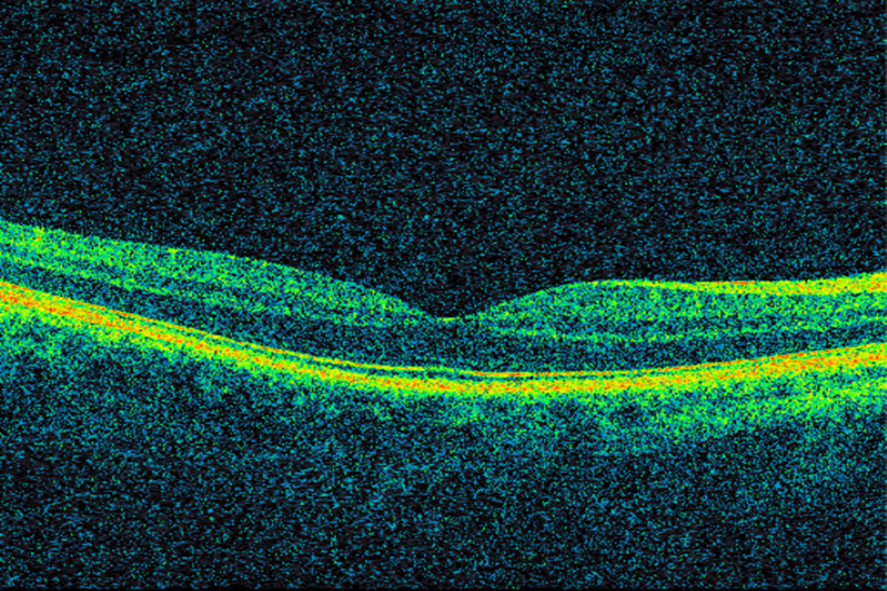

Samtidig som bevacizumab ble tatt i bruk på kreftpasienter, ble VEGF-hemmeren pegaptanib (Macugen) godkjent i USA for behandling av våt aldersrelatert makuladegenerasjon (3). Pegaptanib nøytraliserer VEGF165, som er en av de fire isoformene av vaskulær endotelial vekstfaktor. Pegaptanib fikk raskt konkurranse. Kort tid etter at bevacizumab ble godkjent for kolorektal kreft, ble det gitt til pasienter med våt makuladegenerasjon. En liten studie viste klar bedring av visus, redusert netthinnetykkelse og mindre lekkasje fra neovaskulære forandringer etter bevacizumab gitt intravenøst (13). Amerikanske øyeleger begynte deretter å injisere medikamentet intravitrealt (direkte i øyets glasslegeme) (14). Norske øyeavdelinger var tidlig ute med å tilby denne behandlingen. Intravitreale injeksjoner med VEGF-hemmere er meget effektivt i behandlingen av våt aldersrelatert makuladegenerasjon og andre øyesykdommer, og innebærer lav risiko for komplikasjoner og bivirkninger (15, 16). I denne sammenhengen må det nevnes at utviklingen av optisk koherens-tomografi (optical coherence tomography, OCT) i øyefaget har hatt stor klinisk, vitenskapelig og økonomisk betydning. Optisk koherens-tomografi er en hurtig og ikke-invasiv undersøkelsesmetode som ved hjelp av lysbølger avbilder øyets anatomiske strukturer med mikrometer-oppløsning (17) (figur 1). Teknologien anvendes i dag innen de fleste av øyefagets underspesialiteter, men især ved diagnostisering og oppfølging av øyesykdommer som rammer netthinnen og den utenforliggende årehinnen. Figur 2 og 3 viser OCT-bilder av makula med våt aldersrelatert makuladegenerasjon i samme pasient før og etter oppstart med anti-VEGF-behandling.

Figur 3 OCT av makula hos samme pasient tre år senere etter gjentatte anti-VEGF-injeksjoner. Det er nå tilnærmet tørre…

Figur 3 OCT av makula hos samme pasient tre år senere etter gjentatte anti-VEGF-injeksjoner. Det er nå tilnærmet tørre forhold. Visus er 0,63.